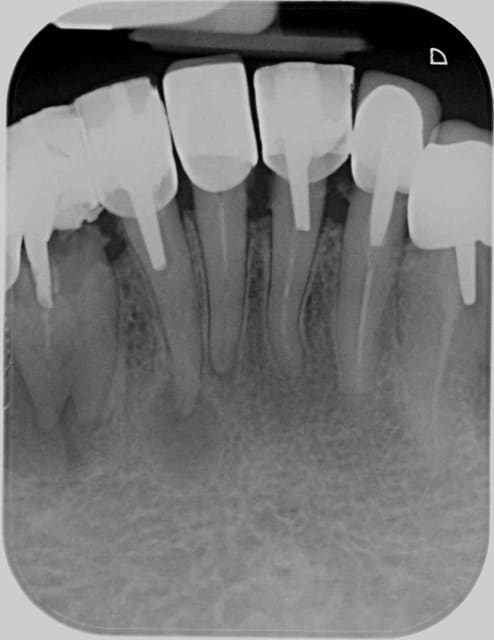

Chez moi, ça sourit moins. A noter la racine double de la 43, peu banale.

Bifide qvsjtb - Eugenol